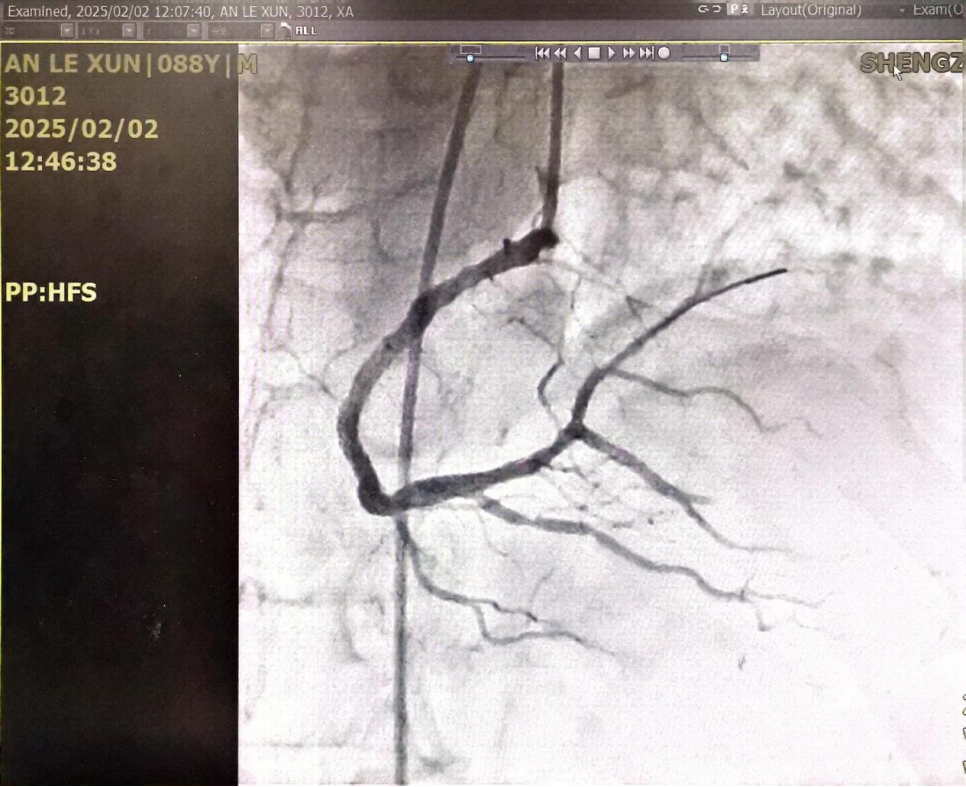

患者病情危重,刻不容缓,在三名医护人员协助下12时将病人紧急转运至介入导管室,导管室医护人员早已严阵以待,在家赶来进行术中监护的左岩霞主任医师也已到位。在大家默契的配合下,韩艳丽主任医师和黄健医师12:13完成冠脉造影,结果显示患者巨大右冠状动脉自中段完全闭塞,12:18球囊到达闭塞部位,经预扩张开通了闭塞的血管,后克服病变钙化、扩张不良等困难,于右冠中段成功植入支架1枚。术后安返病房,患者胸痛明显缓解,心电图ST段回落,病情逐渐稳定。

图4:术前造影提示RCA中段完全闭塞